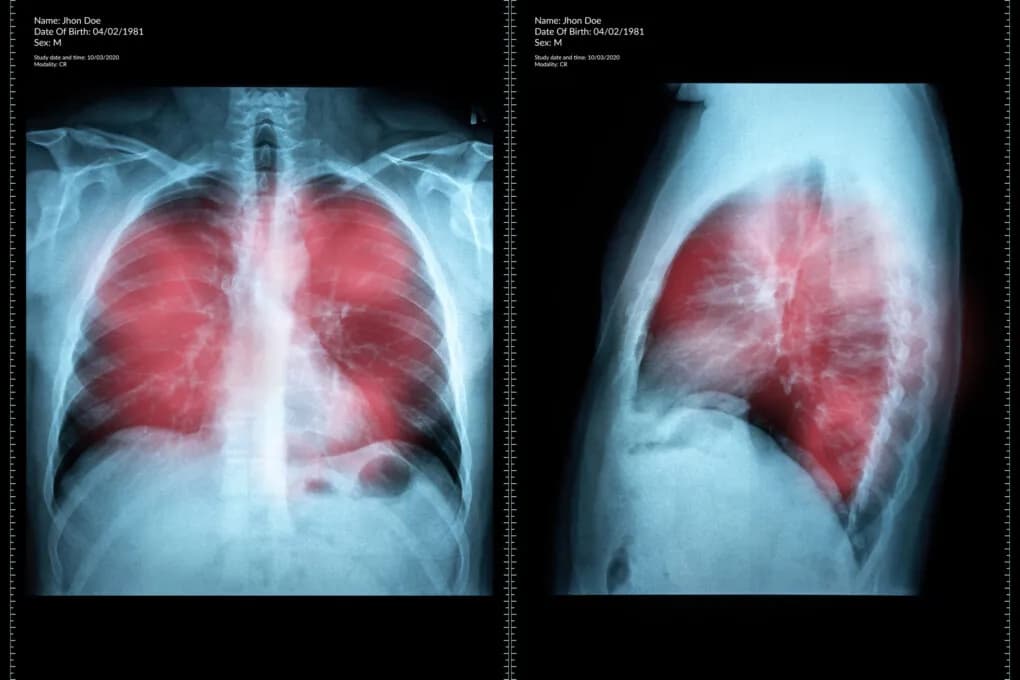

Najważniejsze objawy raka płuc: pierwsze niepokojące sygnały choroby

Poznaj najważniejsze objawy raka płuc, które powinny wzbudzić Twój niepokój. Dowiedz się, jak odróżnić pierwsze symptomy od zwykłego przeziębienia i kiedy należy pilnie skonsultować się z lekarzem.